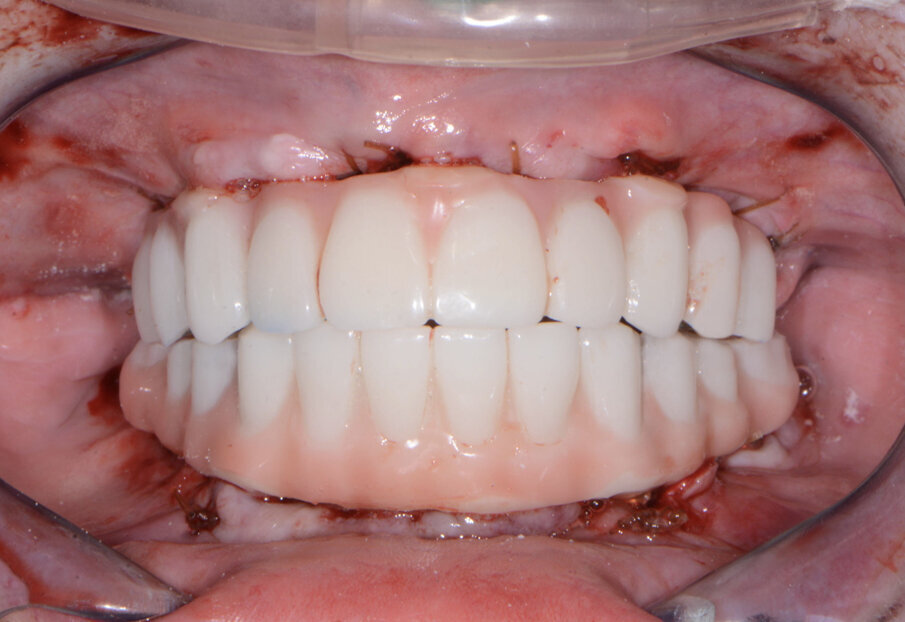

The maxillary provisional restoration was tried in to verify a passive fit over the temporary abutments. Once fit had been confirmed, trimmed dental dam pieces were placed to avoid the restoration (Fig. 11) from locking on during the relining procedure with REBASE III FAST set hard reline material (Tokuyama Dental). After the material had polymerised, the immediate provisional restoration was removed and any access material was removed with the Torque Plus laboratory handpiece (Aseptico) and an acrylic bur (Komet). The same procedures were accomplished in the mandibular arch (Figs. 12–14). Once trimmed and polished, the provisional restorations were seated and tightened with a torque wrench at 15 Ncm (Fig. 15). The access openings were filled in three-quarters of the way with Teflon tape, followed by Cavit filling material (3M ESPE). A postoperative panoramic radiograph was taken immediately after the surgery (Fig. 16).

A few days later, the patient returned for her postoperative appointment with very little discomfort, swelling or bruising. She was very pleased with her new maxillary and mandibular fixed provisional restorations. The occlusion was further checked and adjusted to confirm that there were no interferences in lateral or protrusive movements. The next step in her treatment would consist of full-arch impressions for the definitive restorations approximately four to five months postoperatively.